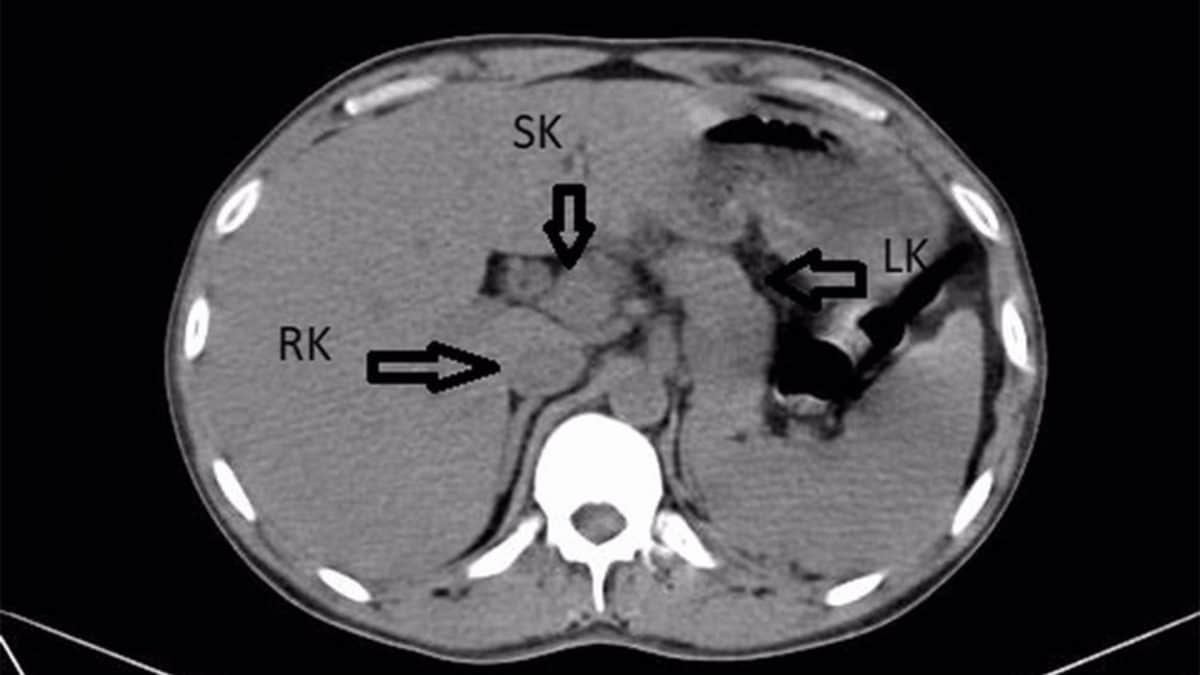

Una visita in ospedale si è trasformata in una scoperta del tutto inaspettata per un 41enne dello Stato indiano del Maharashtra. L’uomo si era presentato al pronto soccorso con febbre alta da alcuni giorni, dolori nella parte bassa della schiena e bruciore durante la minzione. Sintomi che avevano fatto pensare subito a un’infezione delle vie urinarie. Gli esami avevano però rivelato qualcosa di molto diverso. Una TC dell’addome aveva mostrato una condizione estremamente rara: l’uomo non aveva due reni, ma tre. Il rene in più non era separato, ma risultava fuso al destro, con una conformazione “a ferro di cavallo” come spiegato dai medici del Jawaharlal Nehru Medical College di Wardha che hanno descritto il caso in un report pubblicato sulla rivista Cureus.

Si tratta, a tutti gli effetti, di un rene in più, con una propria struttura, anche se non sempre funziona in modo indipendente. Nel caso descritto, la configurazione era tuttavia insolita: il rene in più era fuso al destro, con forma a ferro di cavallo.

Come precisato dai medici del Jawaharlal Nehru Medical College di Wardha, “la presenza di un rene extra è un’anomalia congenita, con meno di cento casi segnalati a livello globale” mentre un terzo rene con una struttura a ferro di cavallo è “riportato molto raramente, con un’incidenza sconosciuta”. Ad oggi, in letteratura, sono stati descritti solo altri cinque casi di questo tipo.